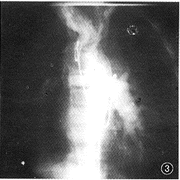

图1~3 男,10岁。X线平片(图1)示单发左位心。导管经奇静脉进入右房及共同心室(图2),又经心室进入主动脉(图3)。造影证实为单心室、共同房室瓣、心室单出口、动脉导管未闭、肺动脉高压